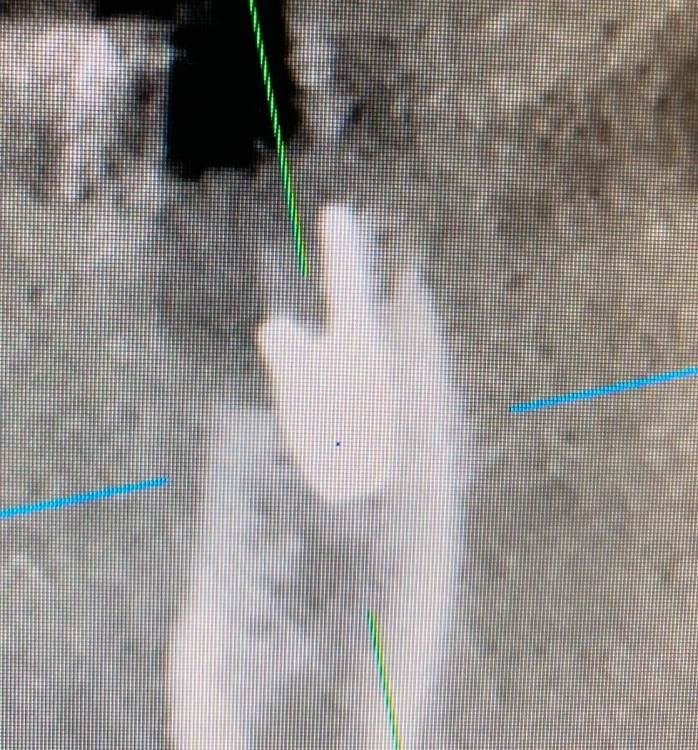

Irouil Опубликовано 11 июля, 2022 Поделиться Опубликовано 11 июля, 2022 (изменено) Не понял - почему недозаглубен? Оба винтыа где-то на 1мм под краем гребня Изменено 11 июля, 2022 пользователем Irouil Ссылка на комментарий

Irouil Опубликовано 11 июля, 2022 Поделиться Опубликовано 11 июля, 2022 (изменено) По фото невозможно понять что там было заглубленно и что нет, на рентгене картина объективнее Я вижу из возможных косяков пл хирургии только избыточно лингвальное позиционирование платформы у одного из винтов, из-за чего стенка очень тонкая - если там случилась резорбция, то иллюзию недозаглубения на фото она вполне может создать К тому же, ТС раньше рассказывал что часто идёт на тунельную твердотканную аугментацию при имплантации в таких случаях, если тут тоже - то для меня неточное позиционирование объясняется именно тунельным подходом и ограниченным обзором по такому поводу. Это, в сущности, единственное, что останавливает меня самого попробовать подобную аугментацию как альтернативу минисосиджу. Но надо услышать ТС, это только мои догадки Изменено 11 июля, 2022 пользователем Irouil Ссылка на комментарий

Irouil Опубликовано 11 июля, 2022 Поделиться Опубликовано 11 июля, 2022 @TIGER какие у Вас на этом фото объективные ориентиры, позволяющие оценить уровень погружения импланта? Такие, чтобы были точно в одной плоскости с оцениваемым положением платформы и в параллельной плоскости к матрице камеры? Это же все равно что объем альвеолярного гребня в области альвеолярной бухты оценивать по плоскостным снимкам Ссылка на комментарий

Irouil Опубликовано 11 июля, 2022 Поделиться Опубликовано 11 июля, 2022 @TIGER ладно, давайте подождём мнения Игоря, на рентгене (который был ДО резорбции и явно объективнее, чем фото ПОСЛЕ неё, да ещё и не в академической проекции) я явного недозаглубения не вижу, хотя глубить, вроде бы, ещё было куда и тут вопрос скорее в том, почему ТС не решил перестраховаться 1 Ссылка на комментарий

Astronaft Опубликовано 12 июля, 2022 Поделиться Опубликовано 12 июля, 2022 (изменено) 06.07.2022 в 14:28, колесников сказал: Протокол отработан как автомат Калашникова,платформа относительно Зенита и вершины гребня,высота уступа,наличие и ширина прикреплённой слизистой. Далее процесс запускается вспять и через два года наблюдаем прирост кости на скосе гребня. Это хорошай заговор-пожелание. В жизни часто не так. По одной простой причине общее здоровье человека влияет намного сильнее. Пародонтологический статус - если есть карманы хоть 5-6мм где-то во рту риск пери-имплантных явлений возрастает. Микробиота слюны, вязкость, диета, качество гигиены, обший воспалительный фон- это сфера влияния пациента. Качественное местное исполнение это хороший фундамент - только одна из составляющих. Астра Профаил - укороченный, асимметричый конус. 3мм с одной стороны, 2мм с другой. Конфигурация перелома закономерна - сами абатменты раскололи высокую стенку от низкой. Я бы предположил что тещины первичны, резорбция это следствие. Изменено 12 июля, 2022 пользователем Astronaft 2 4 Ссылка на комментарий